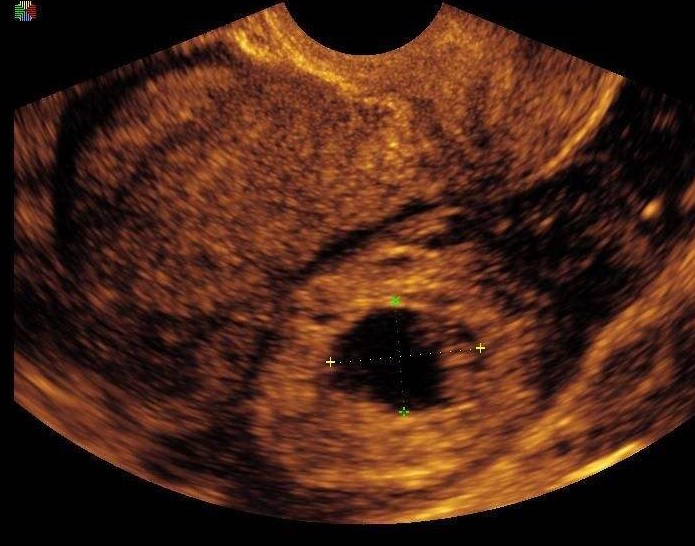

• 超声检查

宫外孕最准确的诊断是超声, 当看到附件区有孕囊,里面有卵黄囊和胚芽,就能确诊 。但是,很多时候孕妈的表现没有那么典型,验尿或是验血发现怀孕后,在附件区发现肿块,这时要高度怀疑宫外孕。

宫外孕有一个“狡猾“”的表现,很迷惑人,20%的宫外孕在宫腔内有“假孕囊”,很像宫内孕的表现,但是里面没有卵黄囊和胚芽,这个是宫腔积液或者积血。